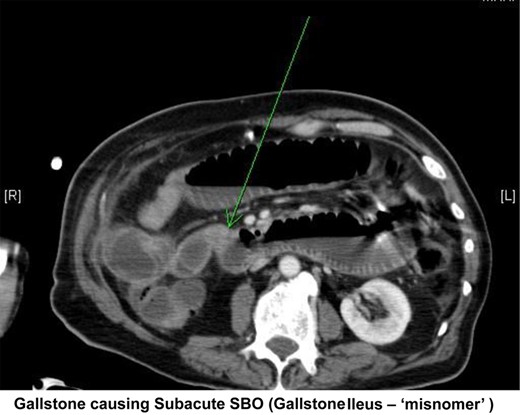

Small bowel obstruction with transition in the distal ileum probably due to obstructing gallstone (Fig. 2).

Transverse section from abdominal CT showing a small bowel obstruction with arrow indicating an intraluminal gallstone.